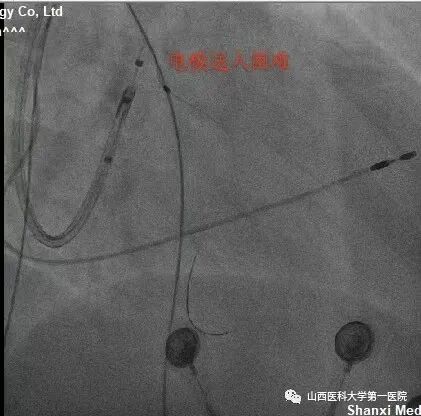

该患者为老年女性,主因反复间断胸闷10余年,加重1周入院。完善相关检查后提示:窦性心律,QRS波宽度187ms、完全左束支传导阻滞形态;心脏彩超显示:左室射血分数:25%,  左室舒末内径:72mm,符合ESC2021CRT指南I类适应证。术中,冠状窦静脉造影发现左室电极靶静脉(左室侧静脉)迂曲,双导丝导丝(Runthrough NS和Pilot50)均无法通过,采用逆向导丝技术,从后静脉逆向进入迂曲的静脉分支及侧支,成功进入左室侧静脉。

该患者冠状窦静脉侧支迂曲严重,前向无法进入左室侧静脉;同时,后静脉逆进入左室侧静脉的分支也非常迂曲,并且多处位置有膈神经刺激,左室电极多次调整,进入不同分支,并调整深度,最终寻找到起搏阈值好且无膈神经刺激位点。赵志强主任医师团队创造性的把冠脉PCI技术应用到手术中,并克服诸多困难,成功完成CRTD植入,期待患者后期心衰症状改善。